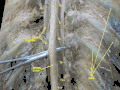

The spinal cord shown in yellow extends through most of the length of the vertebral column to connect the brain with peripheral nerves.